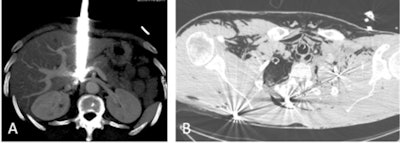

Two cases that underline the importance of CT examinations in ballistic assessment of trauma. A: Stab trauma coming in close contact with the inferior vena cava. multiple gunshot trauma (B). All images courtesy of the Drs. Mathieu Di Bisceglie, Kathia Chaumoître, and JFR e-Quotidien.

Two cases that underline the importance of CT examinations in ballistic assessment of trauma. A: Stab trauma coming in close contact with the inferior vena cava. multiple gunshot trauma (B). All images courtesy of the Drs. Mathieu Di Bisceglie, Kathia Chaumoître, and JFR e-Quotidien.In nonstable patients, first-line emergency imaging exams -- chest x-ray, pleuropulmonary ultrasound, focused assessment with sonography for trauma (FAST) echo -- are now most often performed by the resuscitation team. Imaging should not cause a delay in the surgical management of the patient.